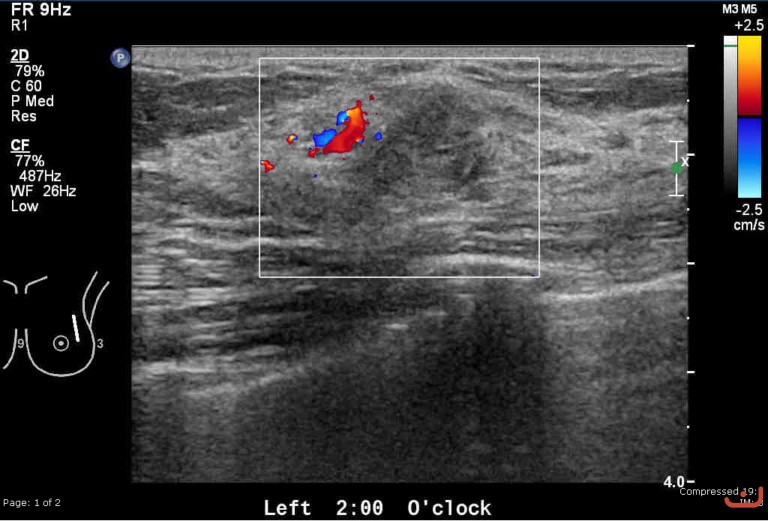

Malignant solid mass

Friday, 22 May 2015